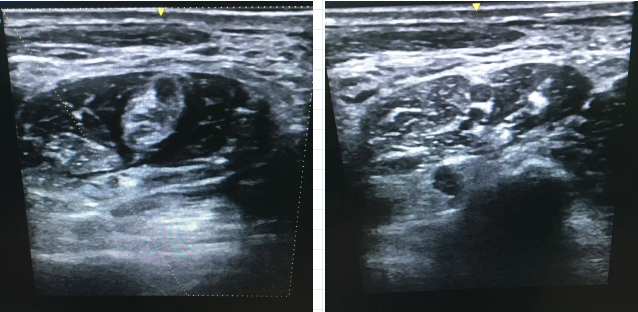

只见手术室麻醉医师手握探头,为耿女士在超声引导下进行了臂丛神经阻滞,全程仅用了不到10分钟就完成了精准麻醉。这项“神操作”为耿女士提供了理想的麻醉效果,减轻了痛苦,避免了神经和血管的损伤,回访时耿女士表示手术时一点也不疼,对麻醉效果特别满意!

在超声引导下“直视”神经走向,

明确神经周围组织。

避开神经周围危险部位,将神经阻滞针准确的穿刺到神经干、神经丛周围。

经穿刺针注入局麻药,阻滞目标神经的神经传导,从而达到精准神经阻滞麻醉的效果。

1、更精准。麻醉医师借助超声引导可直观地了解穿刺部位的神经、肌肉及血管的位置,引导穿刺针准确进针,提高操作成功率。